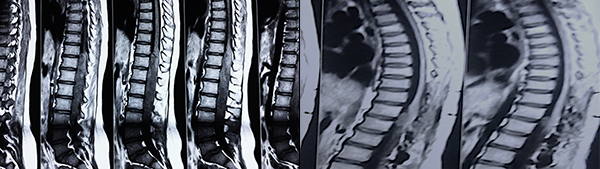

Respecto del monitoreo intraoperatorio, la utilidad del registro de potenciales evocados, Onda D o Electromiografía dependerá no solo de la obtención de respuestas sino también del diálogo entre el cirujano y el neurofisiólogo,11-13 debido al fenómeno de falso negativo y positivo como se muestra en la Tabla 4. El cirujano recibe la información con retraso al evento y en ocasiones las maniobras de “reanimación” medular (irrigación con suero tibio, corticoides, etc.) no son concluyentes produciendo el abandono de una resección factible. La laminoplastía busca favorecer la restitución del alineamiento espinal, pero debe mantenerse un control, en particular en tumores de la unión cérvico dorsal, sobre el desarrollo o acentuación de escoliosis (Figura 3), en ocasiones presente al diagnóstico y que se acentúa en la evolución posoperatoria.13,16

Figura 7: Caso 6. Astrocitoma Pilocítico cervical. Resección subtotal por caída de PESS. Falso Positivo.

Figura 8: Caso 12. Enf de Von Hippel Lindau. Hemangioblastoma cervical. Se observa otra lesión a nivel del Culmen cerebeloso.